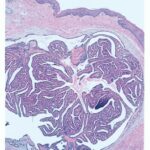

Hidradenoma papilliferum = الغدوم العرقي الحليمي